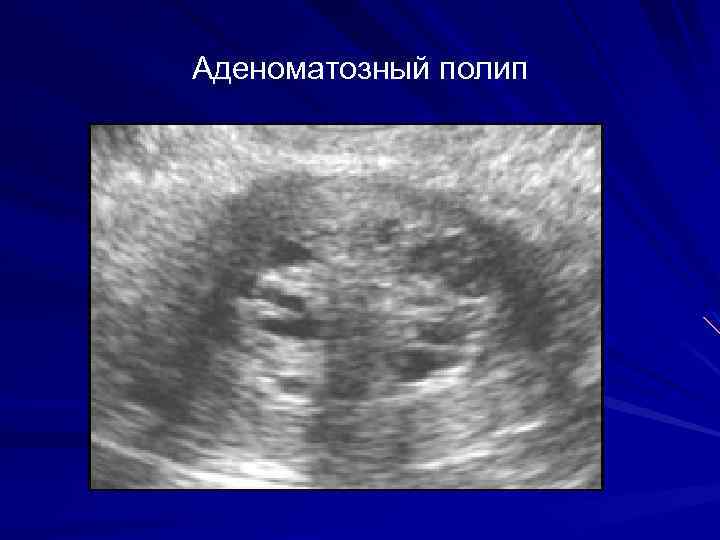

Медицинская диагностика: Гиперплазия эндометрия на УЗИ